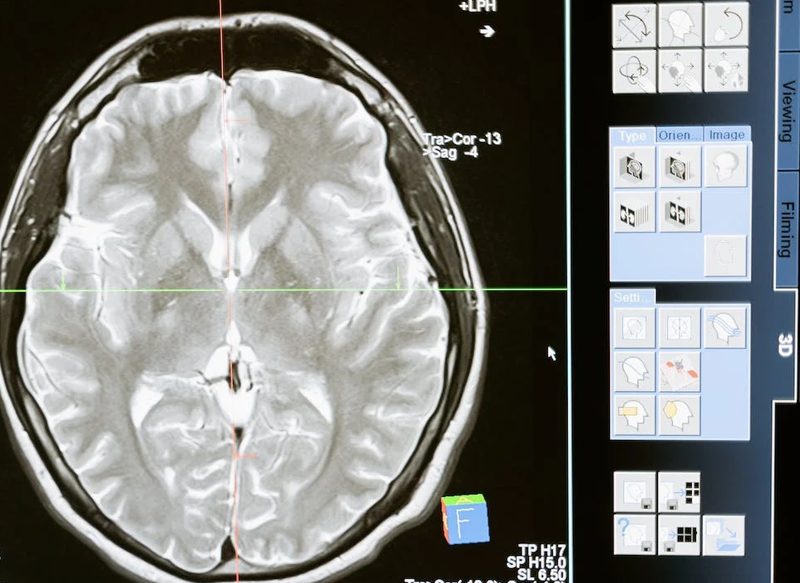

En una nueva investigación, que ha sido publicada en la revista científica Neurology, se han analizado 31 ensayos clínicos que han demostrado cambios en el volumen cerebral con diferentes tipos de fármacos antiamiloides contra el Alzheimer. Asimismo, se relaciona el encogimiento del cerebro con un efecto secundario más conocido en los fármacos, el edema cerebral, que no acostumbra a tener síntomas.

Este estudio señala a los inhibidores de secretasa y los anticuerpos monoclonales, que se incluyen en algunos de los fármacos más conocidos contra la enfermedad, como el propio Lecanemab, Aducanumab y Donanemab, este último rechazado en Estados Unidos en el pasado mes de enero.